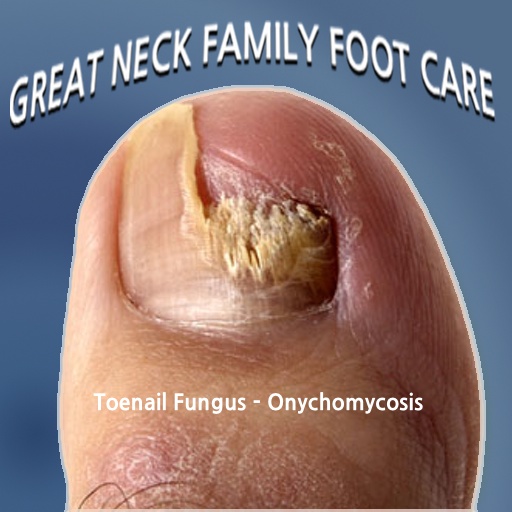

Toenail fungus is a condition that is relatively easy to diagnose. If …

If your toenails are discolored, thick, or cracking, you may have …